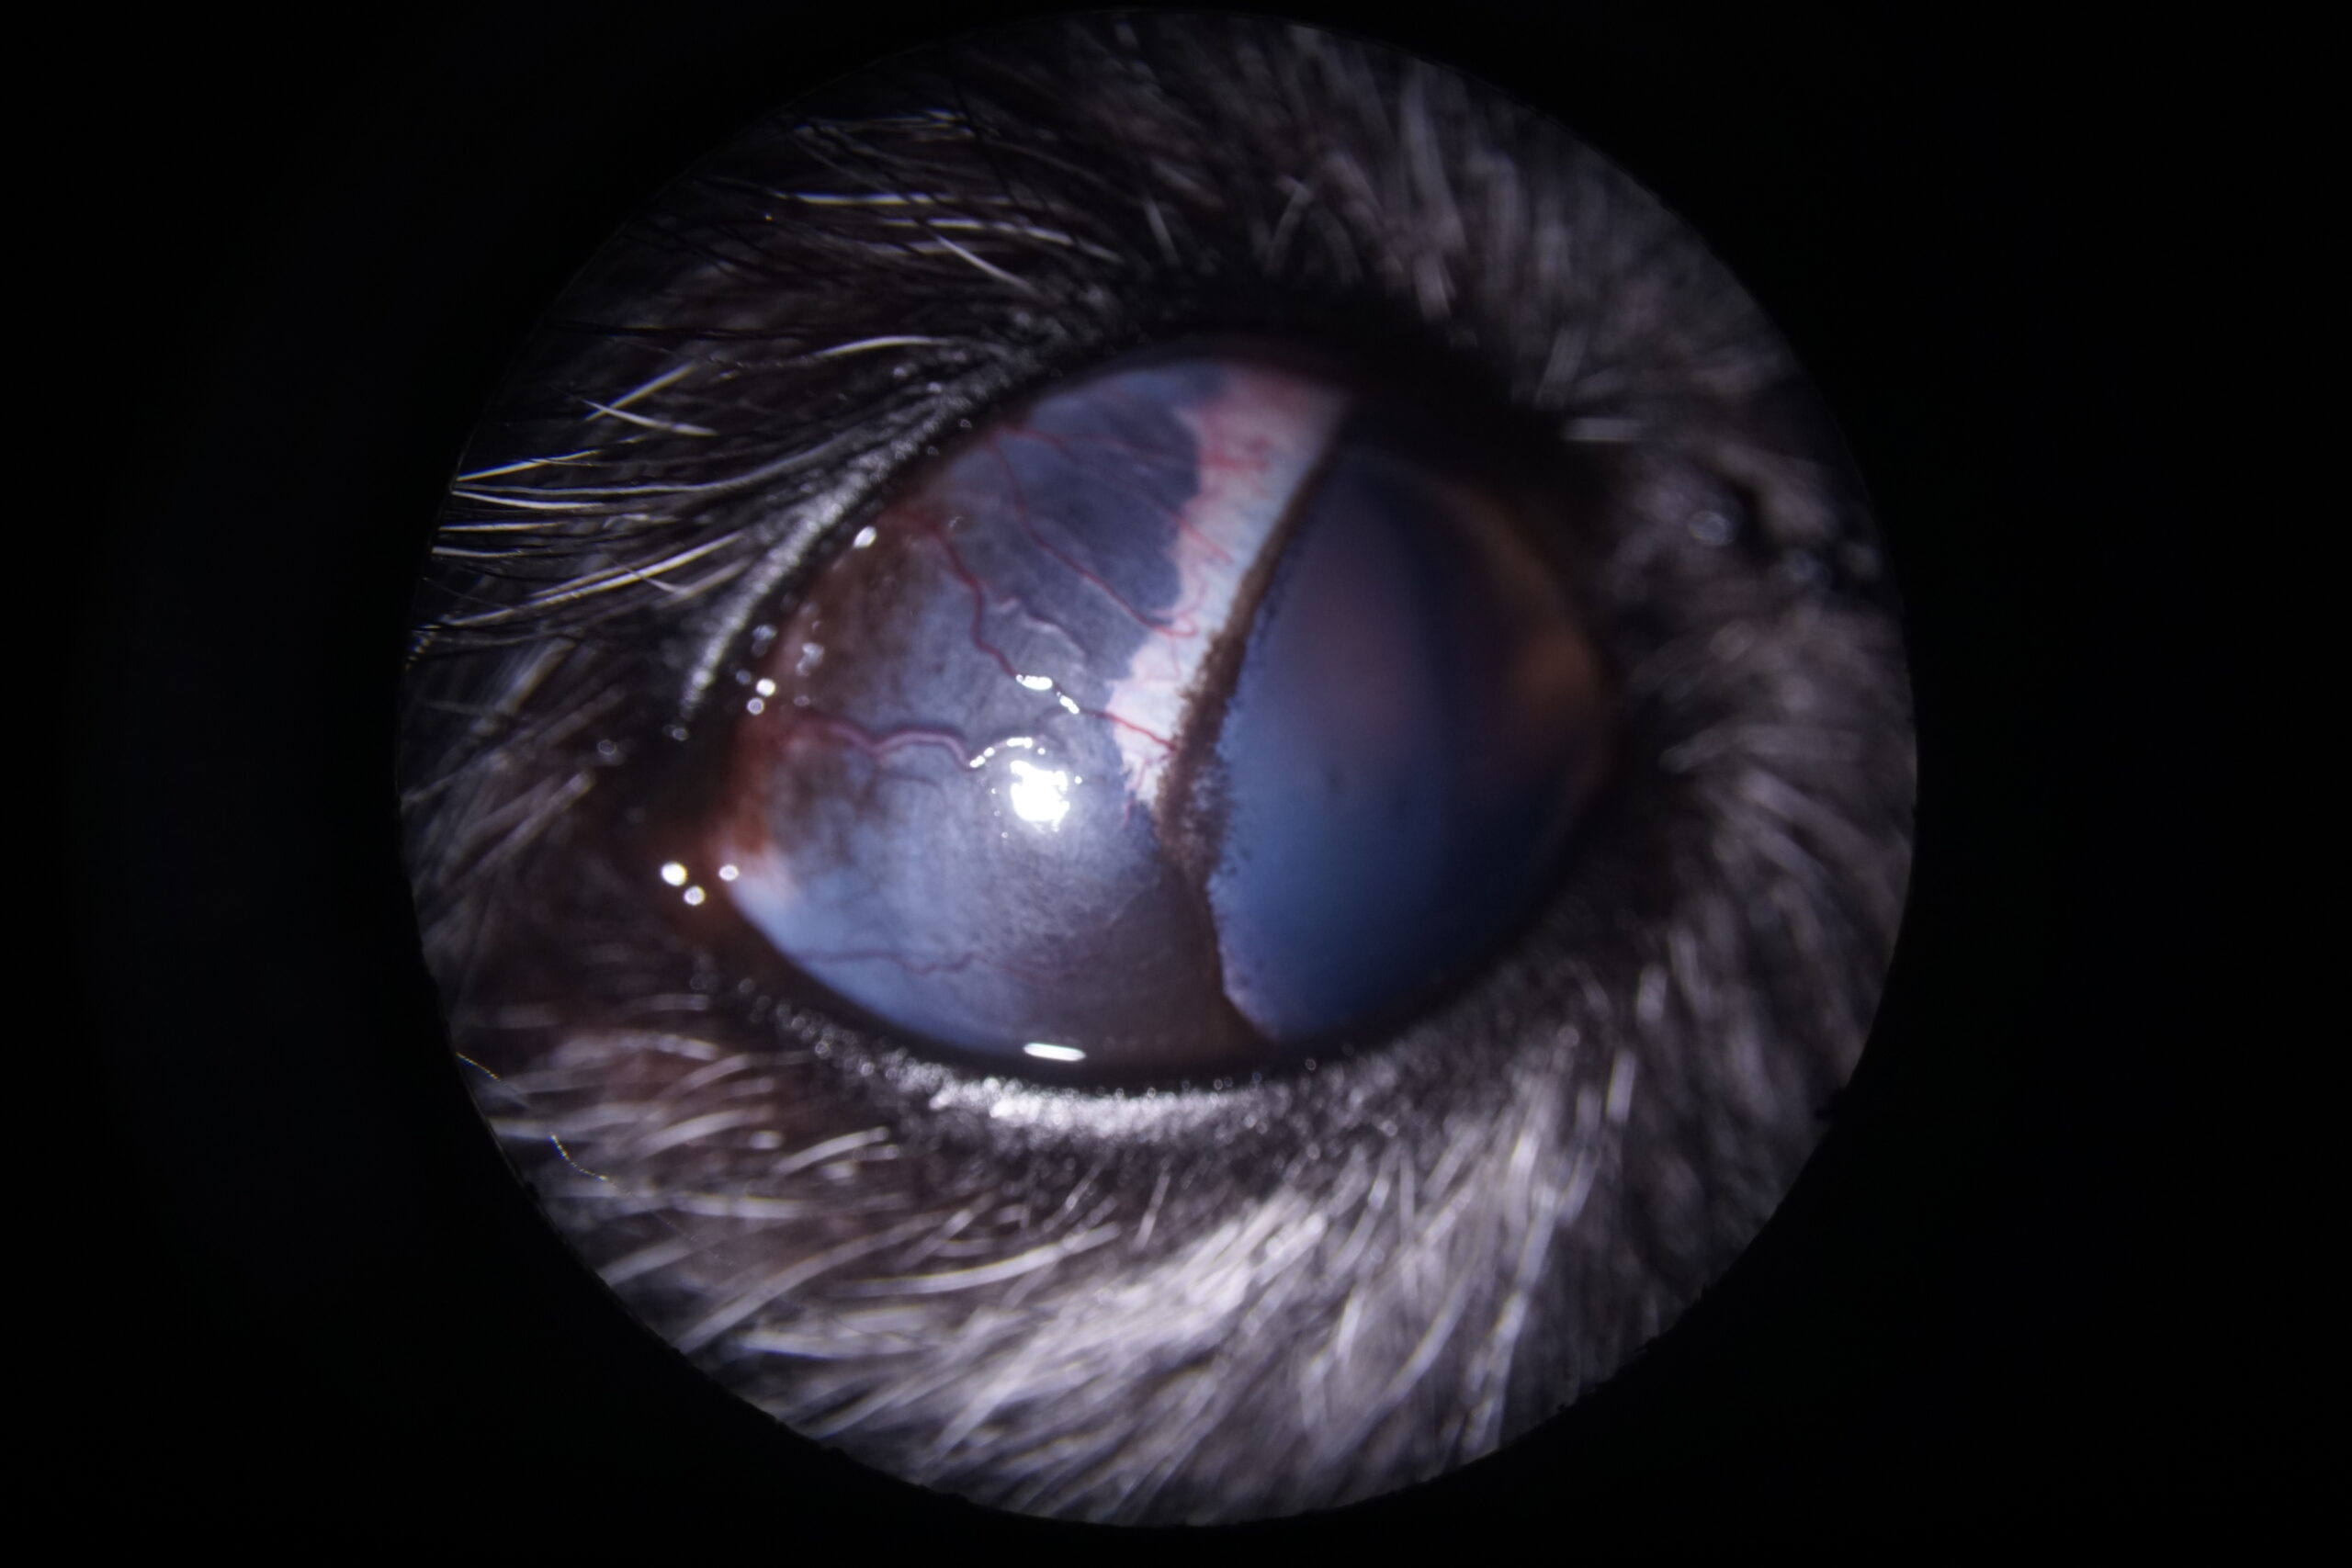

Un chien Cairn Terrier femelle de 10 ans a été présentée en consultation pour l’évaluation d’un glaucome évoluant depuis quelques semaines et ne répondant pas au traitement médical prescrit jusqu’alors (association d’un bétabloquant et d’un inhibiteur de l’anhydrase carbonique par voie locale). A l’examen, la vision a été considérée comme abolie avec absence de réponse à la menace et à l’éblouissement du côté droit. Les photographies 2a et 2b montrent l’aspect de l’œil au moment de la consultation. La photographie 2c est une vue gonioscopique de l’angle iridocornéen à travers une lentille de Koeppe de 17mm.

La pupille est dilatée et ne se contracte pas à la lumière, à tel point qu’il n’est pas visible sur la photographie. Des foyers pigmentés sont visibles sur la capsule antérieure du cristallin. La vue latérale montre un envahissement de la sclère par du pigment. La vue gonioscopique confirme la forte dilatation de la pupille. Les structures qui composent habituellement l’angle iridocornéen sont complètement désorganisées. Le ligament pectiné n’est plus visible et la fente ciliaire a été progressivement comblée par du pigment. Les procès ciliaires sont aussi épaissis et recouverts de pigment.